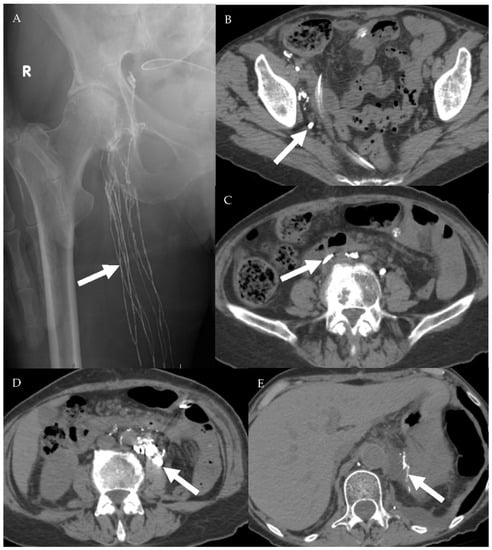

4.2.1. Conventional Lymphangiography (CL)